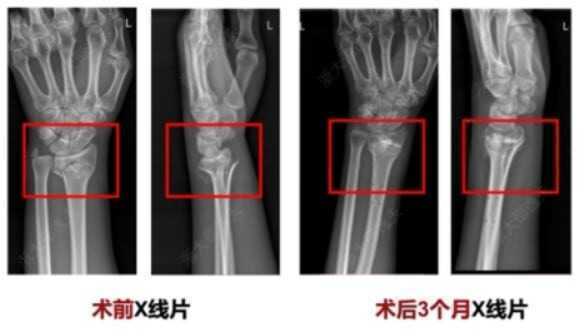

Một trong những ca điển hình là bệnh nhân bị gãy cổ tay do tai nạn sinh hoạt. Thay vì phải phẫu thuật đặt nẹp kim loại, bác sĩ chỉ thực hiện một vết rạch nhỏ dài 3 cm, sau đó tiêm Bone-02 vào vị trí tổn thương.

Toàn bộ quá trình chỉ kéo dài vài phút, và khi tái khám sau ba tháng, vết gãy đã hoàn toàn liền xương, không cần can thiệp thêm. Đặc biệt, bệnh nhân không gặp biến chứng hay phản ứng phụ nào, điều thường thấy ở các ca cấy ghép kim loại truyền thống.